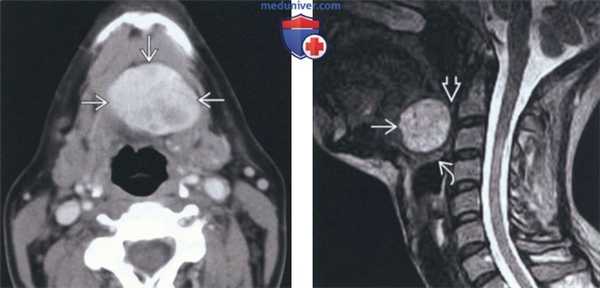

(Слева) На аксиальной КТ с КУ в области дна по средней линии определяется объемное образование с четкими контурами, представленное эктопической тканью щитовидной железы неоднородной плотности (может быть сопоставимо с ранними изменениями при зобе).

(Справа) На сагиттальной MPT (STIR, срединный срез) в основании языка визуализируется объемное образование с неоднородным гиперинтенсивным сигналом, заполняющее валлекулу. В этом случае язычная щитовидная железа обусловливает значительное сужение просвета ротоглотки, смещая надгортанник кзади и книзу.